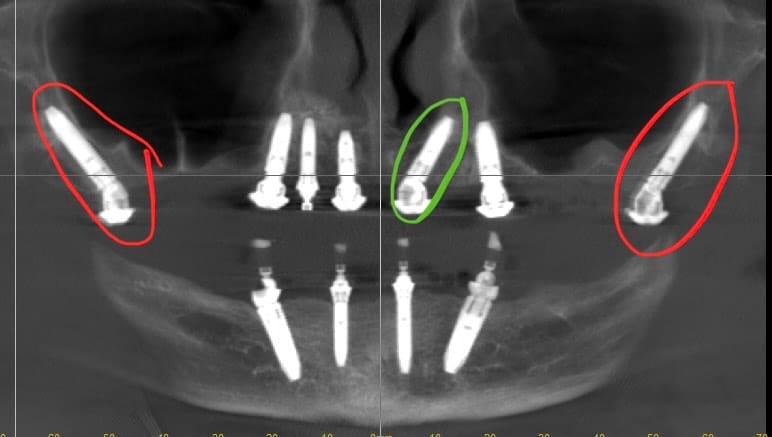

Egy néhány hónappal ezelőtti esetünk. Hatalmas csonthiányai miatt sokadik helyen járt problémájával, igényeivel a páciens- Németországban is. Fontos volt neki, hogy azonnali foga legyen, ne kelljen hosszadalmas csontpótlást végezni…mi lettünk a “nyerők”…

A zöld (ún. paranazális) és pirosan (pterygoidális) bekarikázott implantátumok behelyezése speciális – 1-1 külön kurzuson tanulhatók műtéti technikáik.

2014-ben Magyarországról én végeztem el legelsőként ill. kaptam Zygoma Certifikátot. Ez 2014-es legelső esetünk 2 db Zygoma implantátummal. a CT 2025 decemberi kontrollon készült, ma is tökéletes.. Műtét után azonnal terheltük.